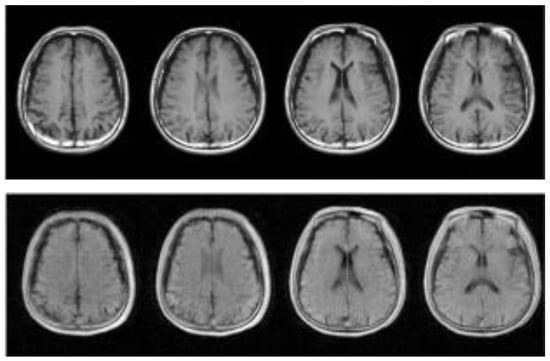

In Section 2.1, for MRI imaging technology, we introduce the advantages. However, MRI scanners rely on complex superconducting electromagnets and excellent electronic equipment for imaging, which leads to high cost, a large area of site occupancy, and demanding imaging site conditions. Therefore, people have begun to promote the development of low-cost MRI technology with ultralow field (ULF) intensity for large-scale medical image detection [53,54], which leads the MRI images’ disadvantage in that most clinical images are lost to computers [55]. Figure 1, Figure 2 and Figure 3 show the differences between T1-weighted images, T2-weighted images, and FLAIR-weighted images based on a high magnetic field, standard MRI images, and an ultralow field MRI, respectively. It can be seen from the comparison that these ultralow field MRI images have low brightness, poor contrast, no obvious details, and considerable noise, which is not convenient for computer and doctor detection.

Figure 2.

The top picture is taken from the T1W strong magnetic field, and the bottom picture is taken from the T1W weak magnetic field in the same position from left to right.